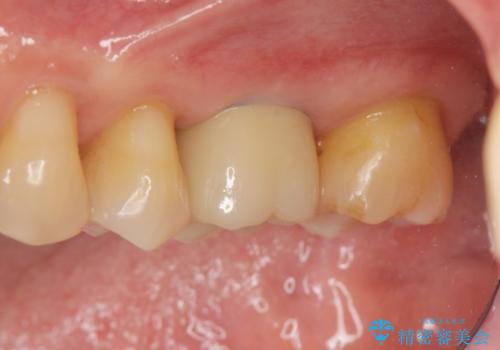

[ 失った歯の機能を回復 ] 奥歯のインプラント治療